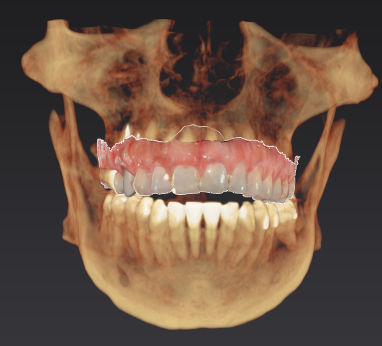

During your initial consultation at Arcadia Perio, Dr. Peterson will review your medical history, perform an oral exam, take digital X-rays, and likely consult your general dentist. Sometimes, a 3D scan is taken with our cone-beam computed tomography scanner to accurately visualize your unique anatomy and plan virtual implant treatment. The initial planning phase is as thorough as possible to optimize long-term success and determine your optimal solution.

Procedure & Same-Day Teeth

The 3D image we took during your consultation is used to create computer-aided guidance with our sophisticated X-Nav system. Visualizing the placement of your dental implants in 3D eliminates guesswork and potential complications. In the skilled hands of Dr. Peterson, proper planning combined with X-Guide Dynamic 3D Navigation during surgery elevates surgical excellence while increasing efficiency and safety. If you received full-mouth dental implants, our customized, streamlined protocol enables Dr. Peterson to fit you with temporary 3D-printed teeth within 24 hours of your surgical procedure.

Implant Treatment Planning

Clinical overview

3D planning

CBCT & planning

Planning detail

Additional planning view